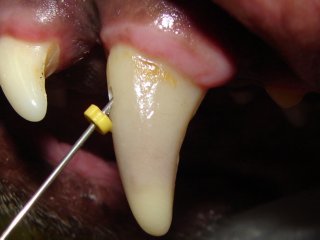

A canine tooth with purplish color change is being cleaned out with an endodontic file.